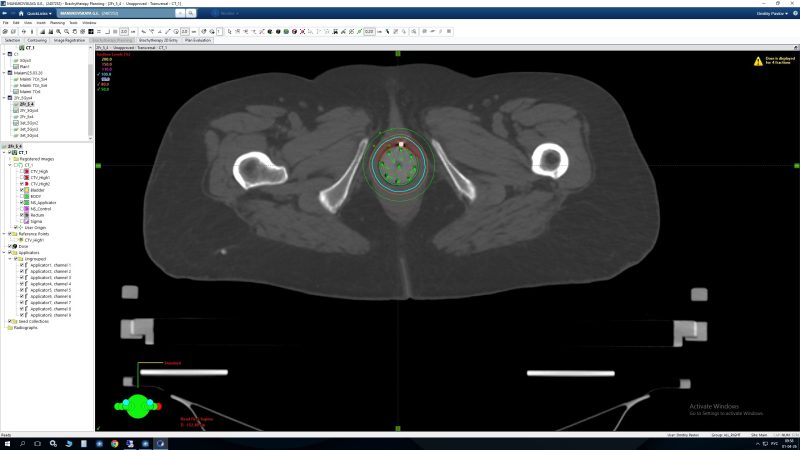

- Еще одной уникальной возможностью брахитерапии является использование ее при лечении рецидивов заболевания или метастатических поражений. Использование многоканального аппликатора позволяет не использовать каналы, которые прилегают к органам риска, что дает возможность максимально снизить дозу на них и уменьшить вероятность побочных эффектов даже при повторном облучении данной области.

Использование всех доступных каналов Исключение каналов, прилегающих к прямой кишке